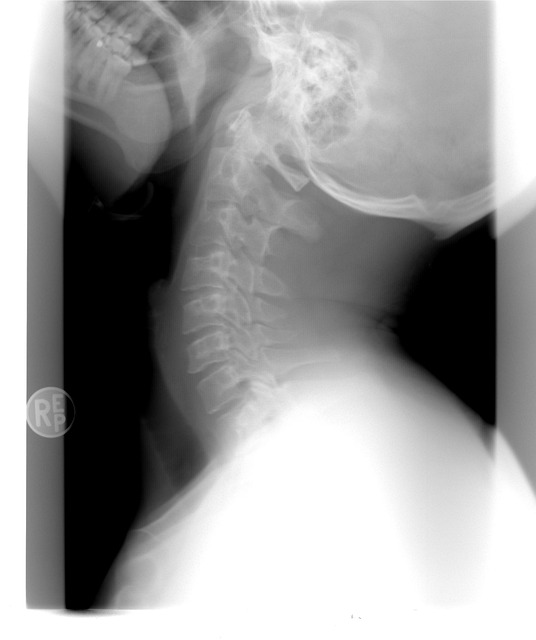

- 영상검사: 엑스레이, 초음파, MRI를 이용해 관절의 염증 상태를 확인합니다.